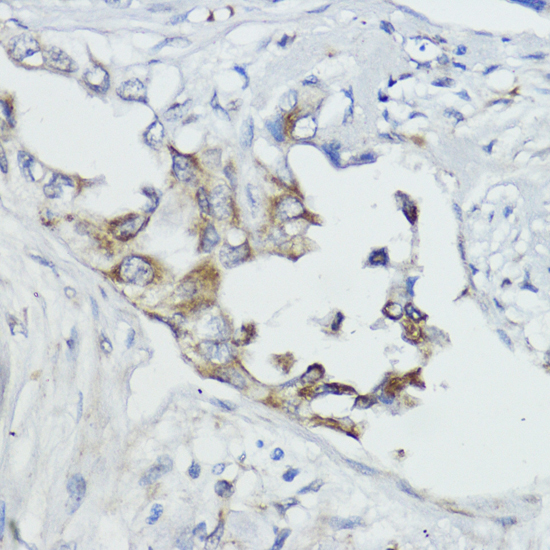

Immunohistochemistry of paraffin-embedded human mammary cancer using FXN / Frataxin antibody.

Immunohistochemistry of paraffin-embedded human colon using FXN / Frataxin antibody.

Immunohistochemistry of paraffin-embedded human lung cancer using FXN / Frataxin antibody. |